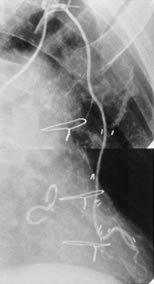

手術直後に造影した内胸動脈です。矢印部位で血管損傷が起こり、途中で血流が無くなっています。幸い、患者さんの症状が落ち着いていたので、経過を見ていました。そして一年後のことです。

一年後の造影では損傷して流れなくなった内胸動脈が見事に流れています。内胸動脈には「自己修復力」があるのだと思います。他の血管ではあまり無いことです。これを見た時は、本当に嬉しかったので、一生懸命英語の論文を書きました。論文を書いて投稿すると「査読」と言って専門家の先生が、評価をしてくれます。ダメ出しをされることも多いのです。この雑誌はアメリカの雑誌ですから、アメリカ人心臓外科医数人に査読して頂いています。皆さん、掲載にO.K.で高評価だったのですが、一人の先生は「こういう現象(内胸動脈の自己修復力)は自分でも数例経験している。珍しいことでは無い。でも論文になるのは初めてだ」と書いてきました。自分たちも似たような経験があったのでしょう。でも、書いたモノ勝ちですから、掲載してくれました。嬉しい出来事でした。